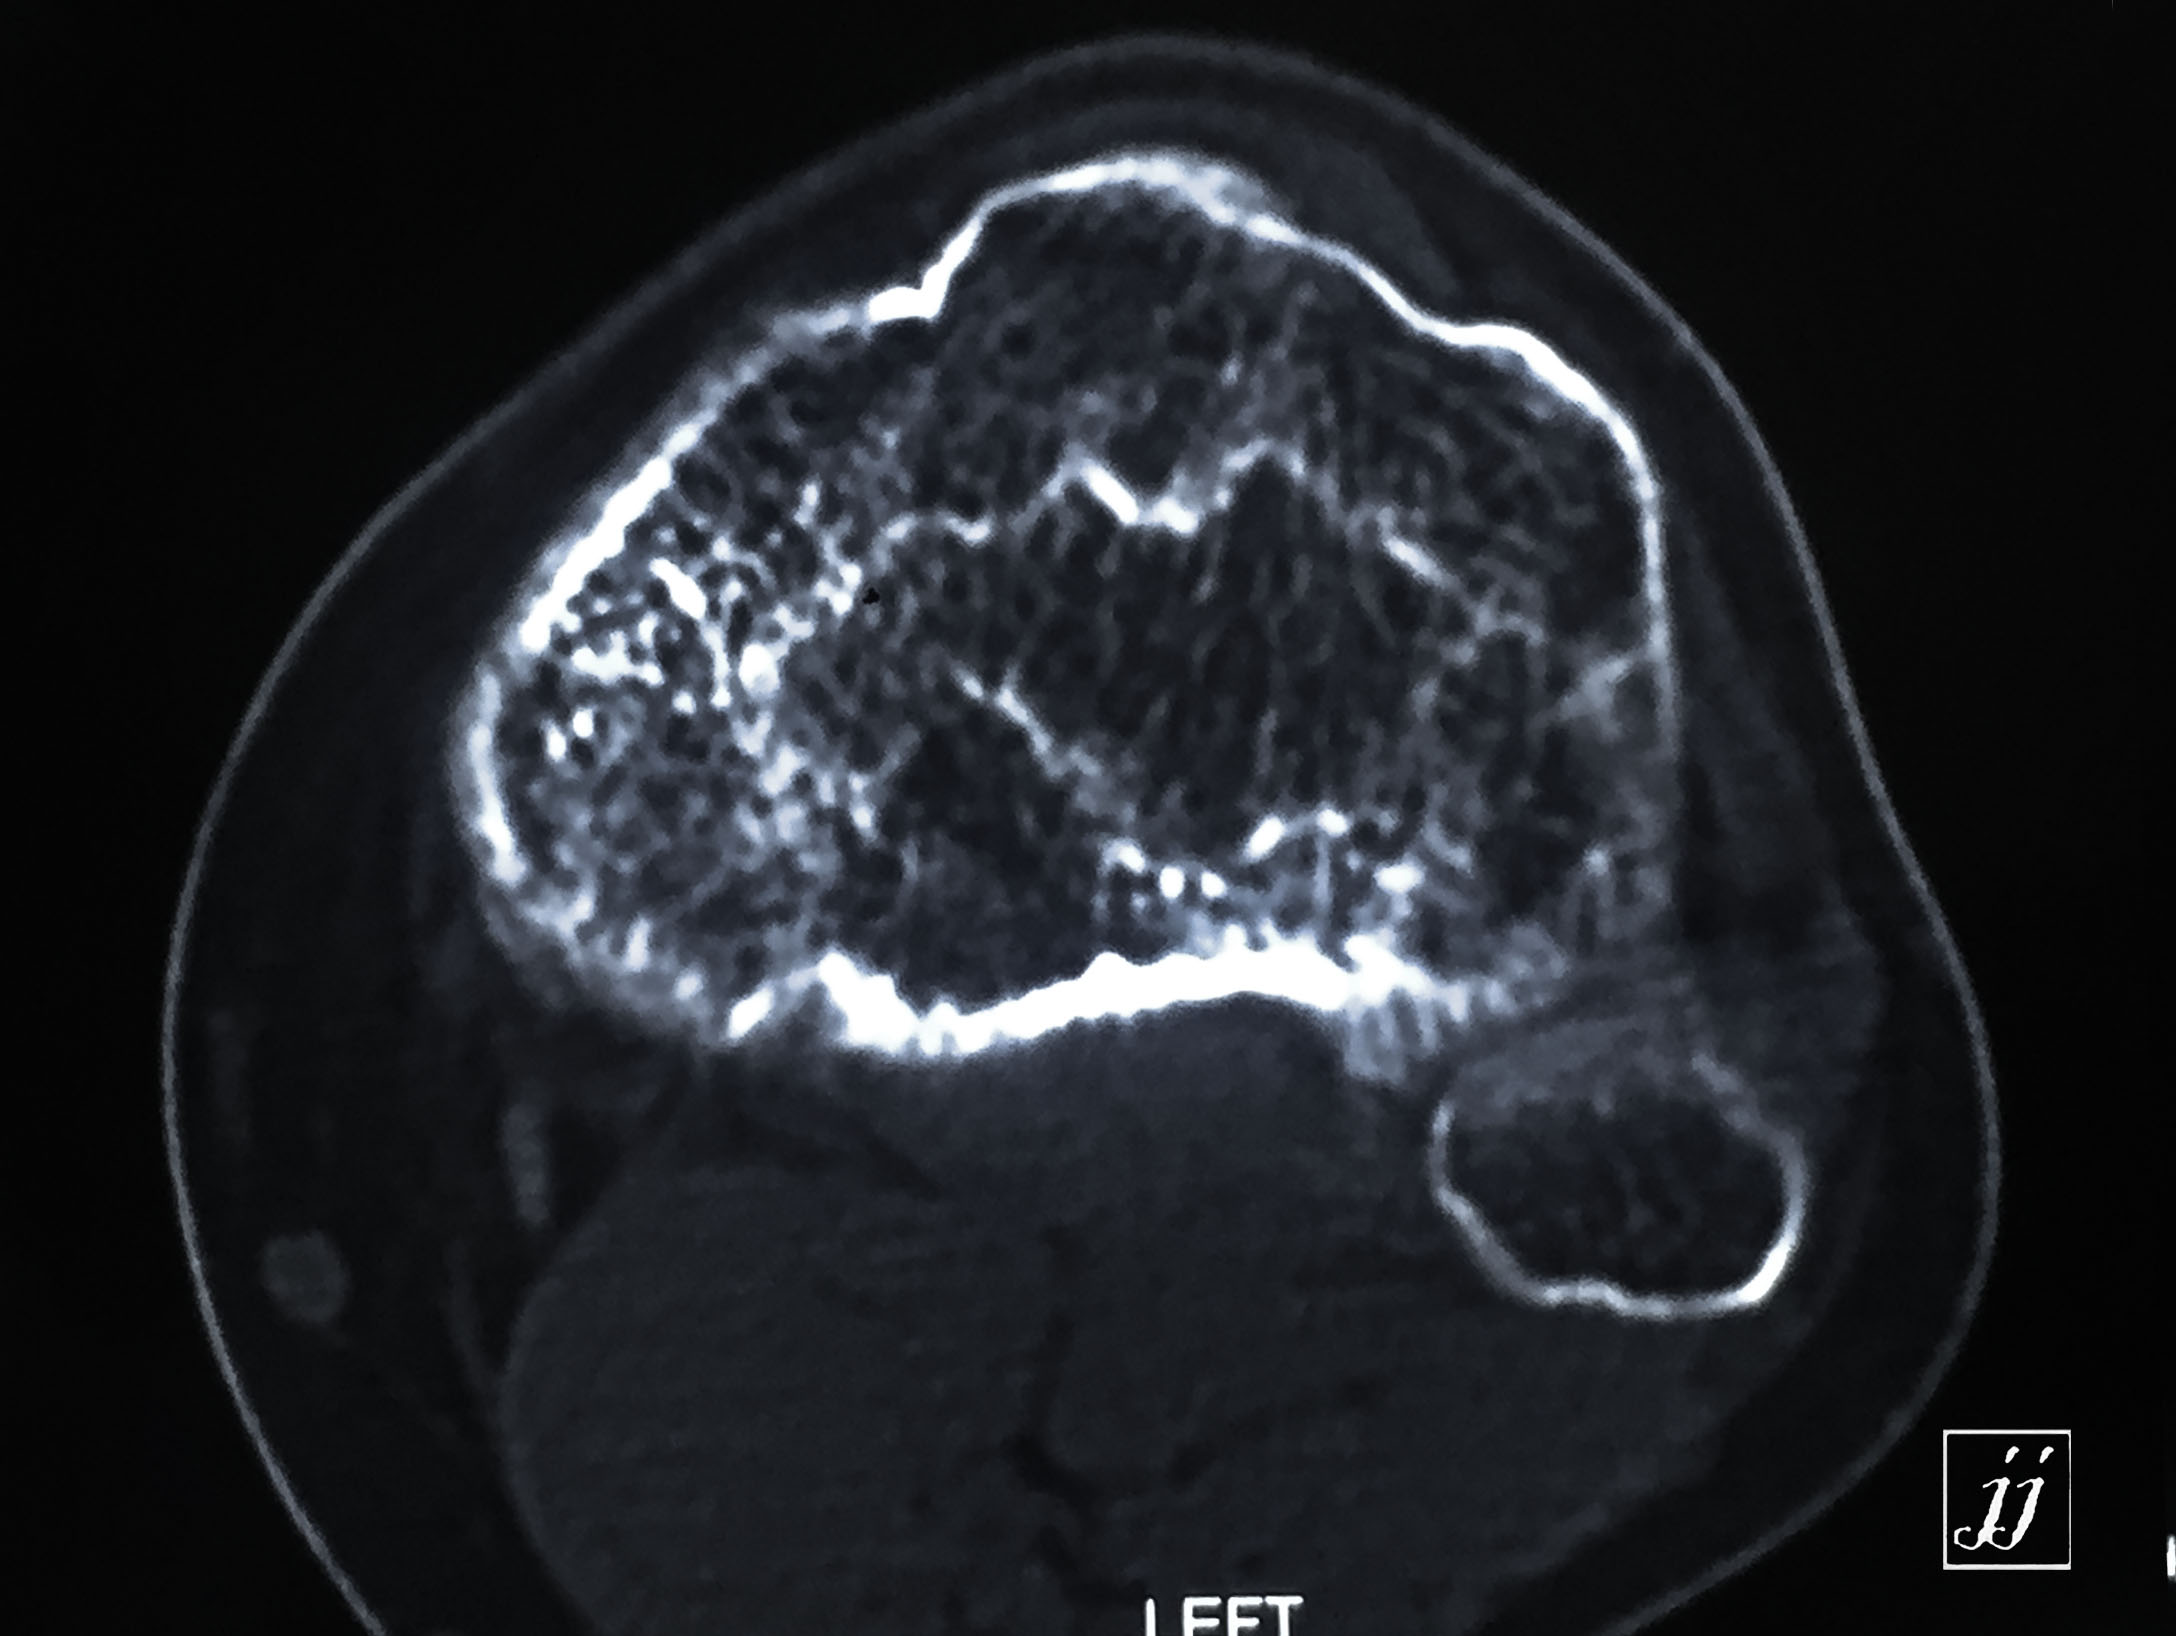

MSK- proximal tibia fracture and infection (28)